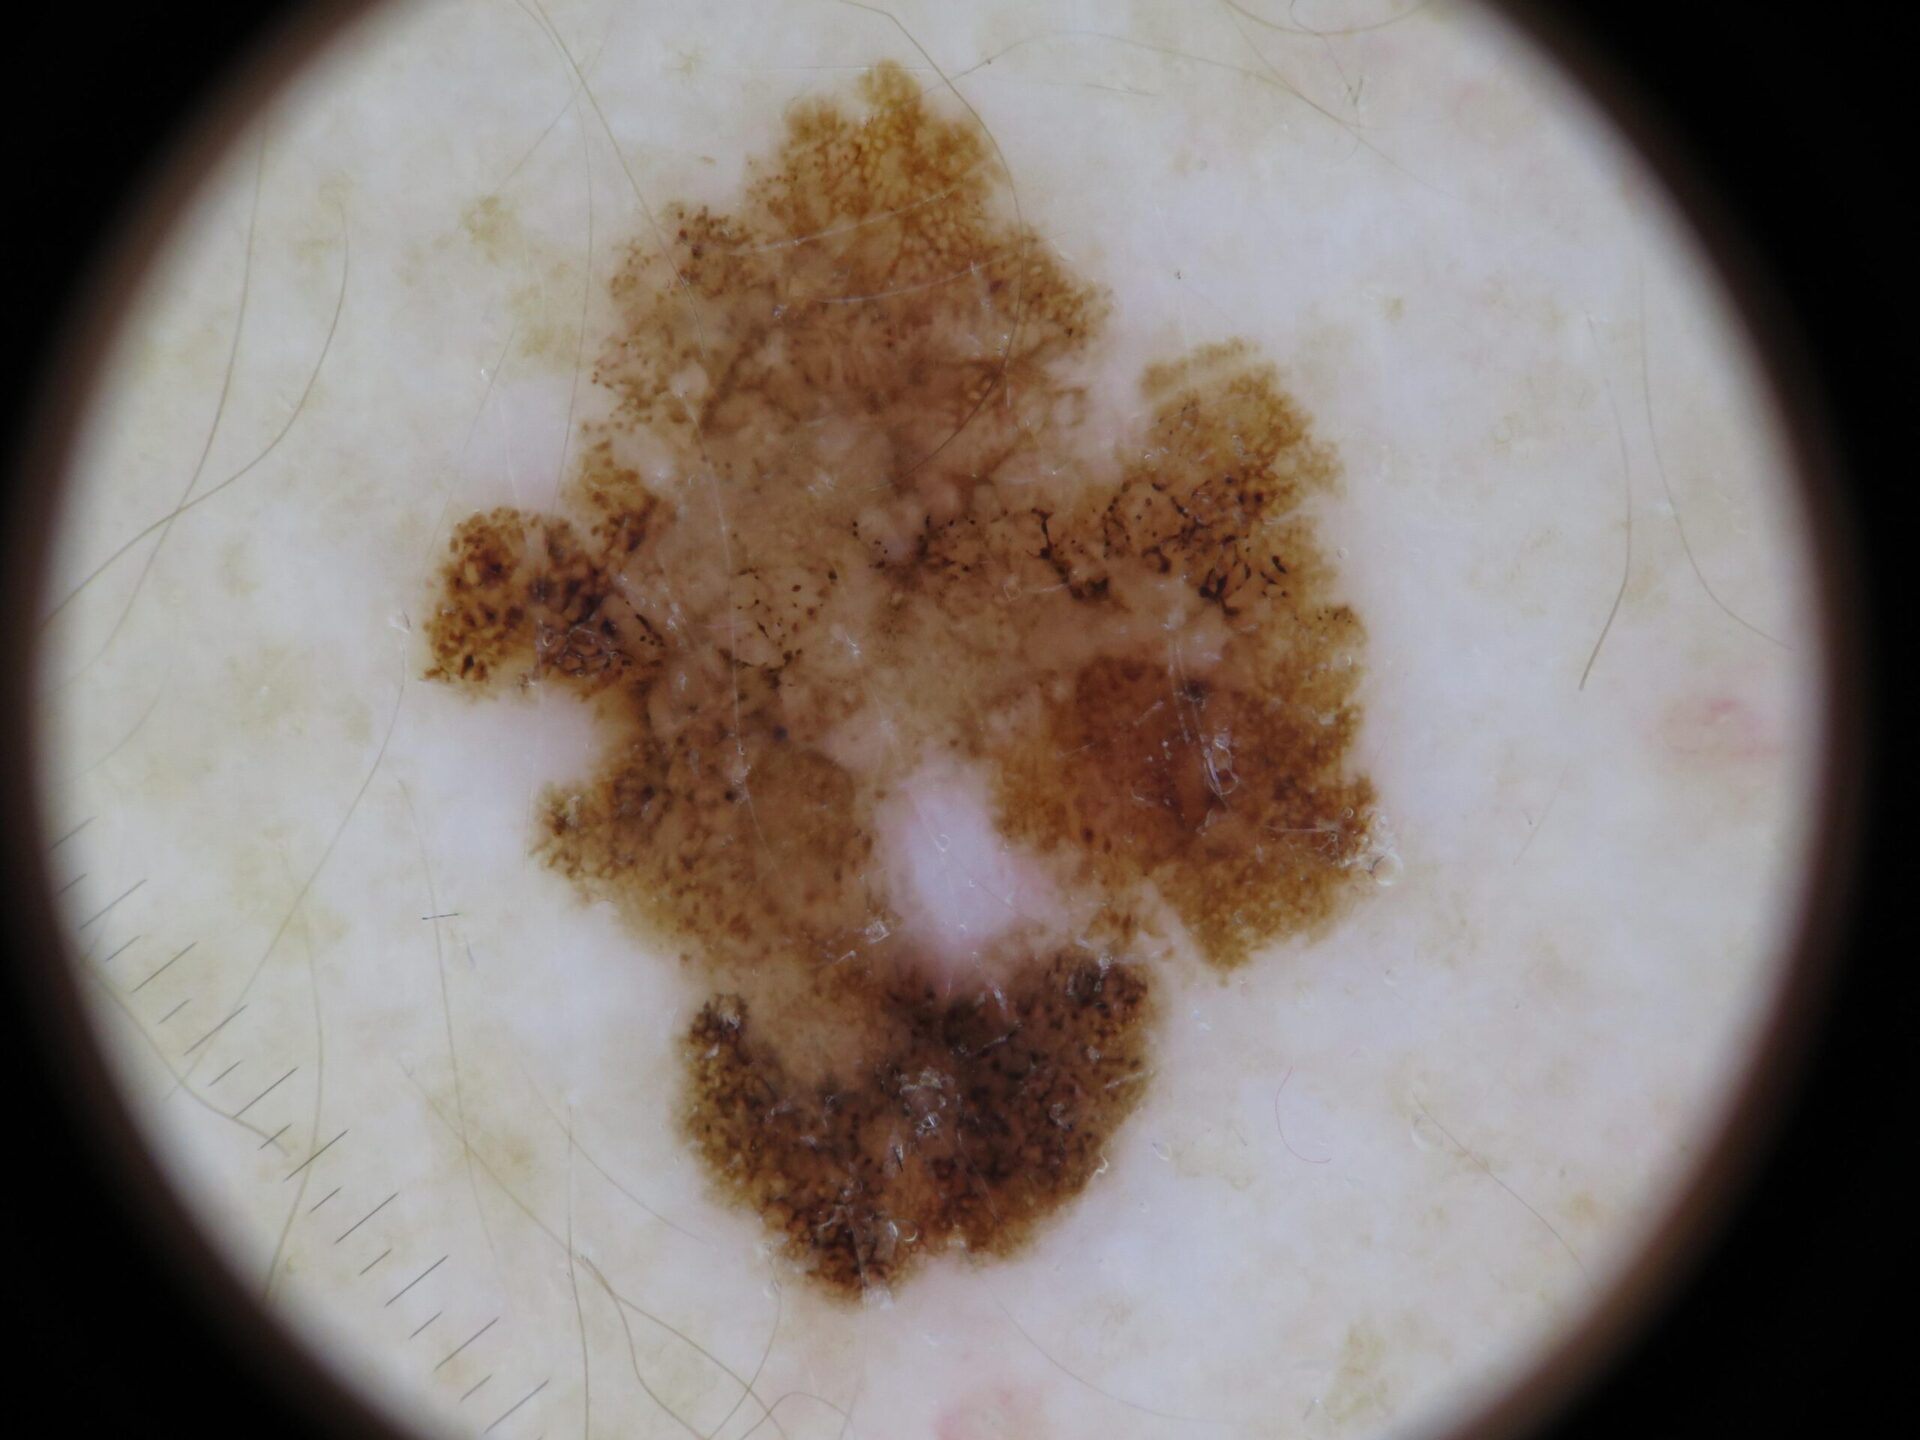

Basal Cell Carcinoma (BCC) Photos

Basal cell carcinoma on the posterior torso. Photo: International Skin Imaging Collaboration at isic-archive.com

Basal cell carcinoma on the neck. Photo: International Skin Imaging Collaboration at isic-archive.com

Basal cell carcinoma on the anterior torso. Photo: International Skin Imaging Collaboration at isic-archive.com

Basal cell carcinoma presenting as an open sore on the ear. Photo: International Skin Imaging Collaboration at isic-archive.com

Basal cell carcinoma presenting as a pink growth. Photo: International Skin Imaging Collaboration at isic-archive.com

Basal cell carcinoma on the leg. Photo: International Skin Imaging Collaboration at isic-archive.com

A small pink growth with a slightly raised, rolled edge and a crusted indentation in the center. (BCC)